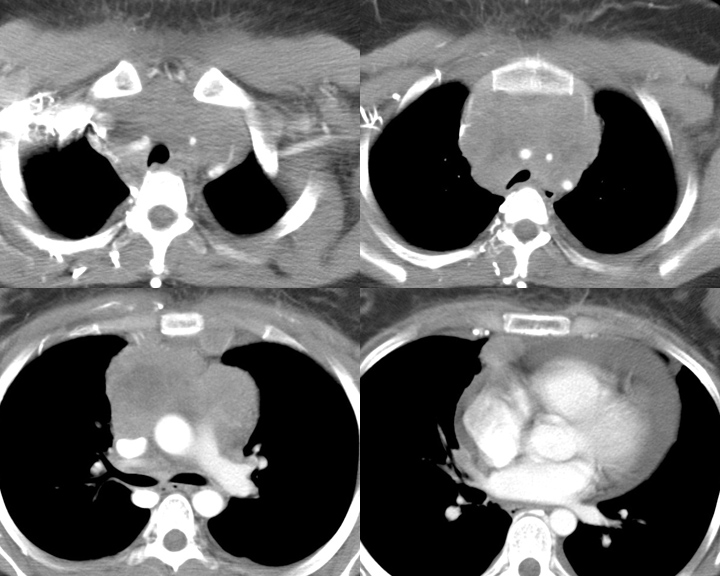

Gallery Mediastinum Lymphoma 6c

6c